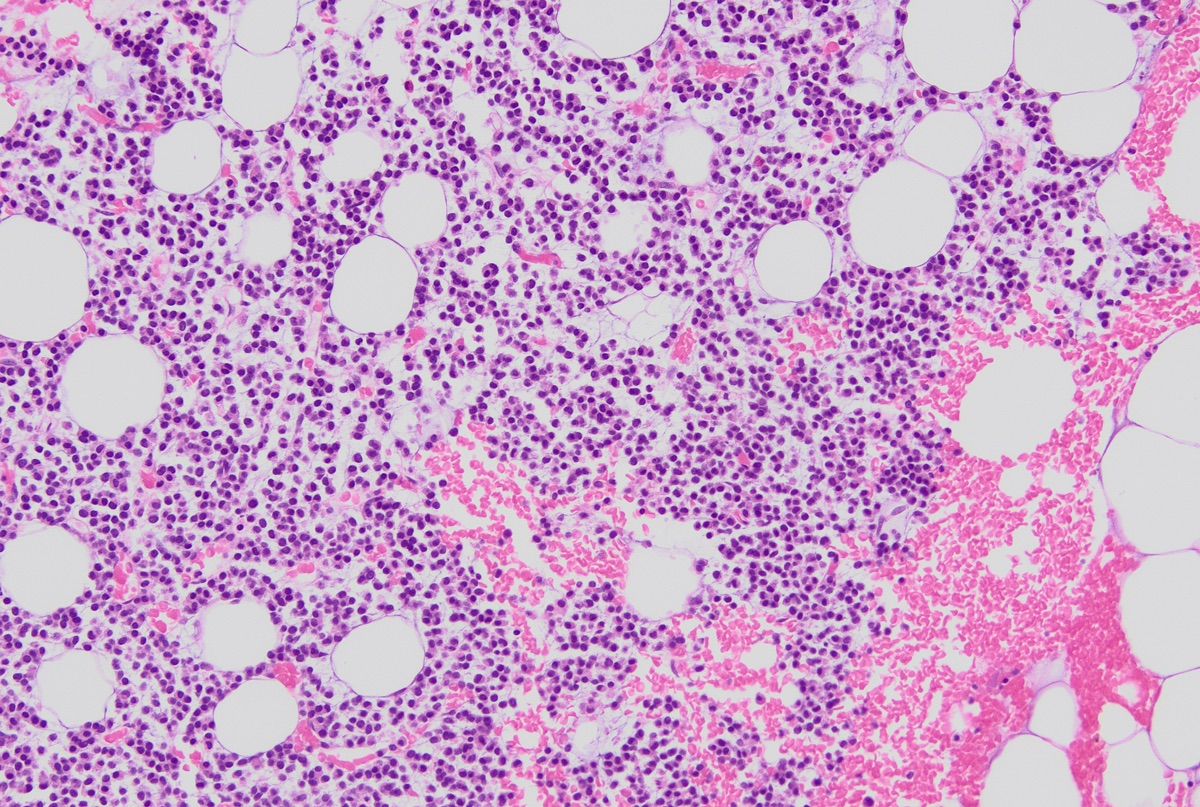

Microscopic (histologic) description

- Core biopsy (Am J Clin Path 1987;87:342):

- Interstitial clusters, nodules or sheets of plasma cells

- Areas of bone marrow may be spared with preserved hematopoiesis, other cases may have diffuse involvement and markedly suppressed hematopoiesis

- Prominent osteoclastic activity may be seen

- IHC to quantify plasma cells (CD138), stains for Ig kappa and lambda to establish clonality

Microscopic (histologic) images

Contributed by Genevieve M. Crane, M.D., Ph.D. and Tapan Bhavsar, M.D., Ph.D.